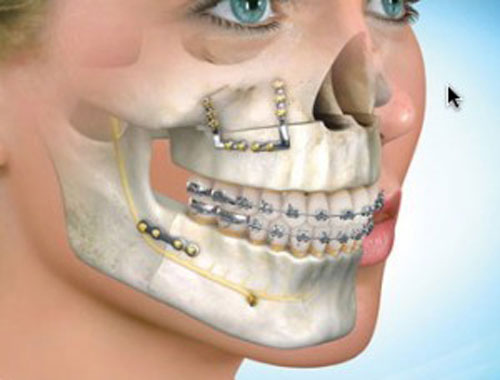

این روش با همکاری جراح فک و صورت و ارتودنتیست انجام میشود. جراحی ارتوگناتیک با جابجا کردن فک فوقانی به سمت بالا، میزان نمایش دندانها و لثهها را کاهش میدهد. این روش تهاجمیتر بوده و برای بیمارانی که دارای ناهماهنگیهای فکی هستند و رشد عمودی بیش از حد فک بالا را تجربه میکنند، ممکن است مناسبترین گزینه باشد.